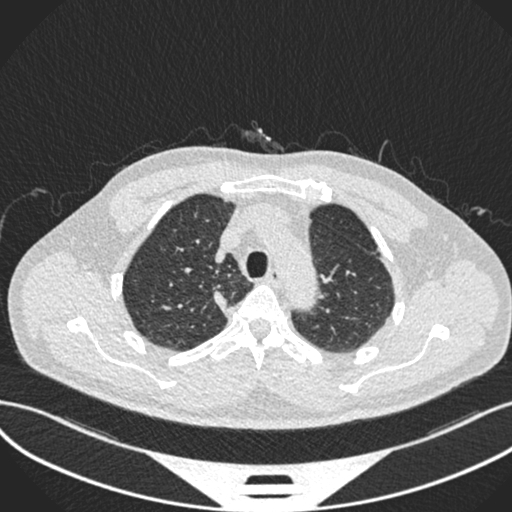

• Analyzes CT scan images using a convolutional neural network

Deep Learning A CNN-based image classifier using a modified ResNet18 trained on lung CT scans.

• ResNet18 model (224×224 RGB input)

Model generalization CT datasets vary significantly in resolution, contrast, and labeling quality. I had to refine preprocessing pipelines to ensure consistent inference.